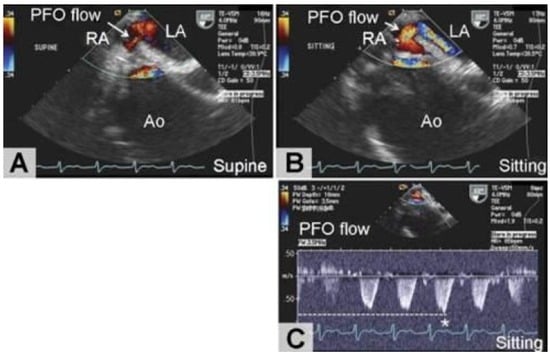

- Nakahira, A.; Matsumura, Y.; Tatsumi, H.; Sasaki, Y.; Hirai, H.; Hanatani, A.; Muro, T.; Yoshiyama, M.; Suehiro, S. Platypnea-orthodeoxia diagnosed by sitting transesophageal echocardiography. Ann. Thorac. Surg. 2010, 89, 1284–1286. [Google Scholar] [CrossRef] [PubMed]